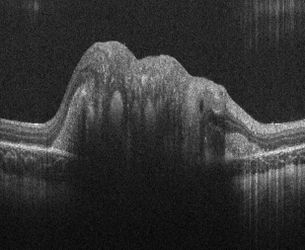

Bioptigen Inc. - сертифицированная ISO 13485 компания по производству медицинского оборудования, которая разрабатывает инновационные решения для офтальмологической визуализации. Системы класса R от компании Bioptigen Envisu (tm) идеально подходят для неинвазивной офтальмологической визуализации животных, от рыбок данио до слонов. Используя маломощный свет в ближнем инфракрасном диапазоне, Envisu в реальном времени генерирует объемные изображения микроструктуры глаза с высоким разрешением от роговицы до сетчатки в реальном времени. Компания Bioptigen получила одобрение CE на продажу своих портативных систем Envisu R2000 для доклинического использования и систем C2000 для клинического использования в ЕС.